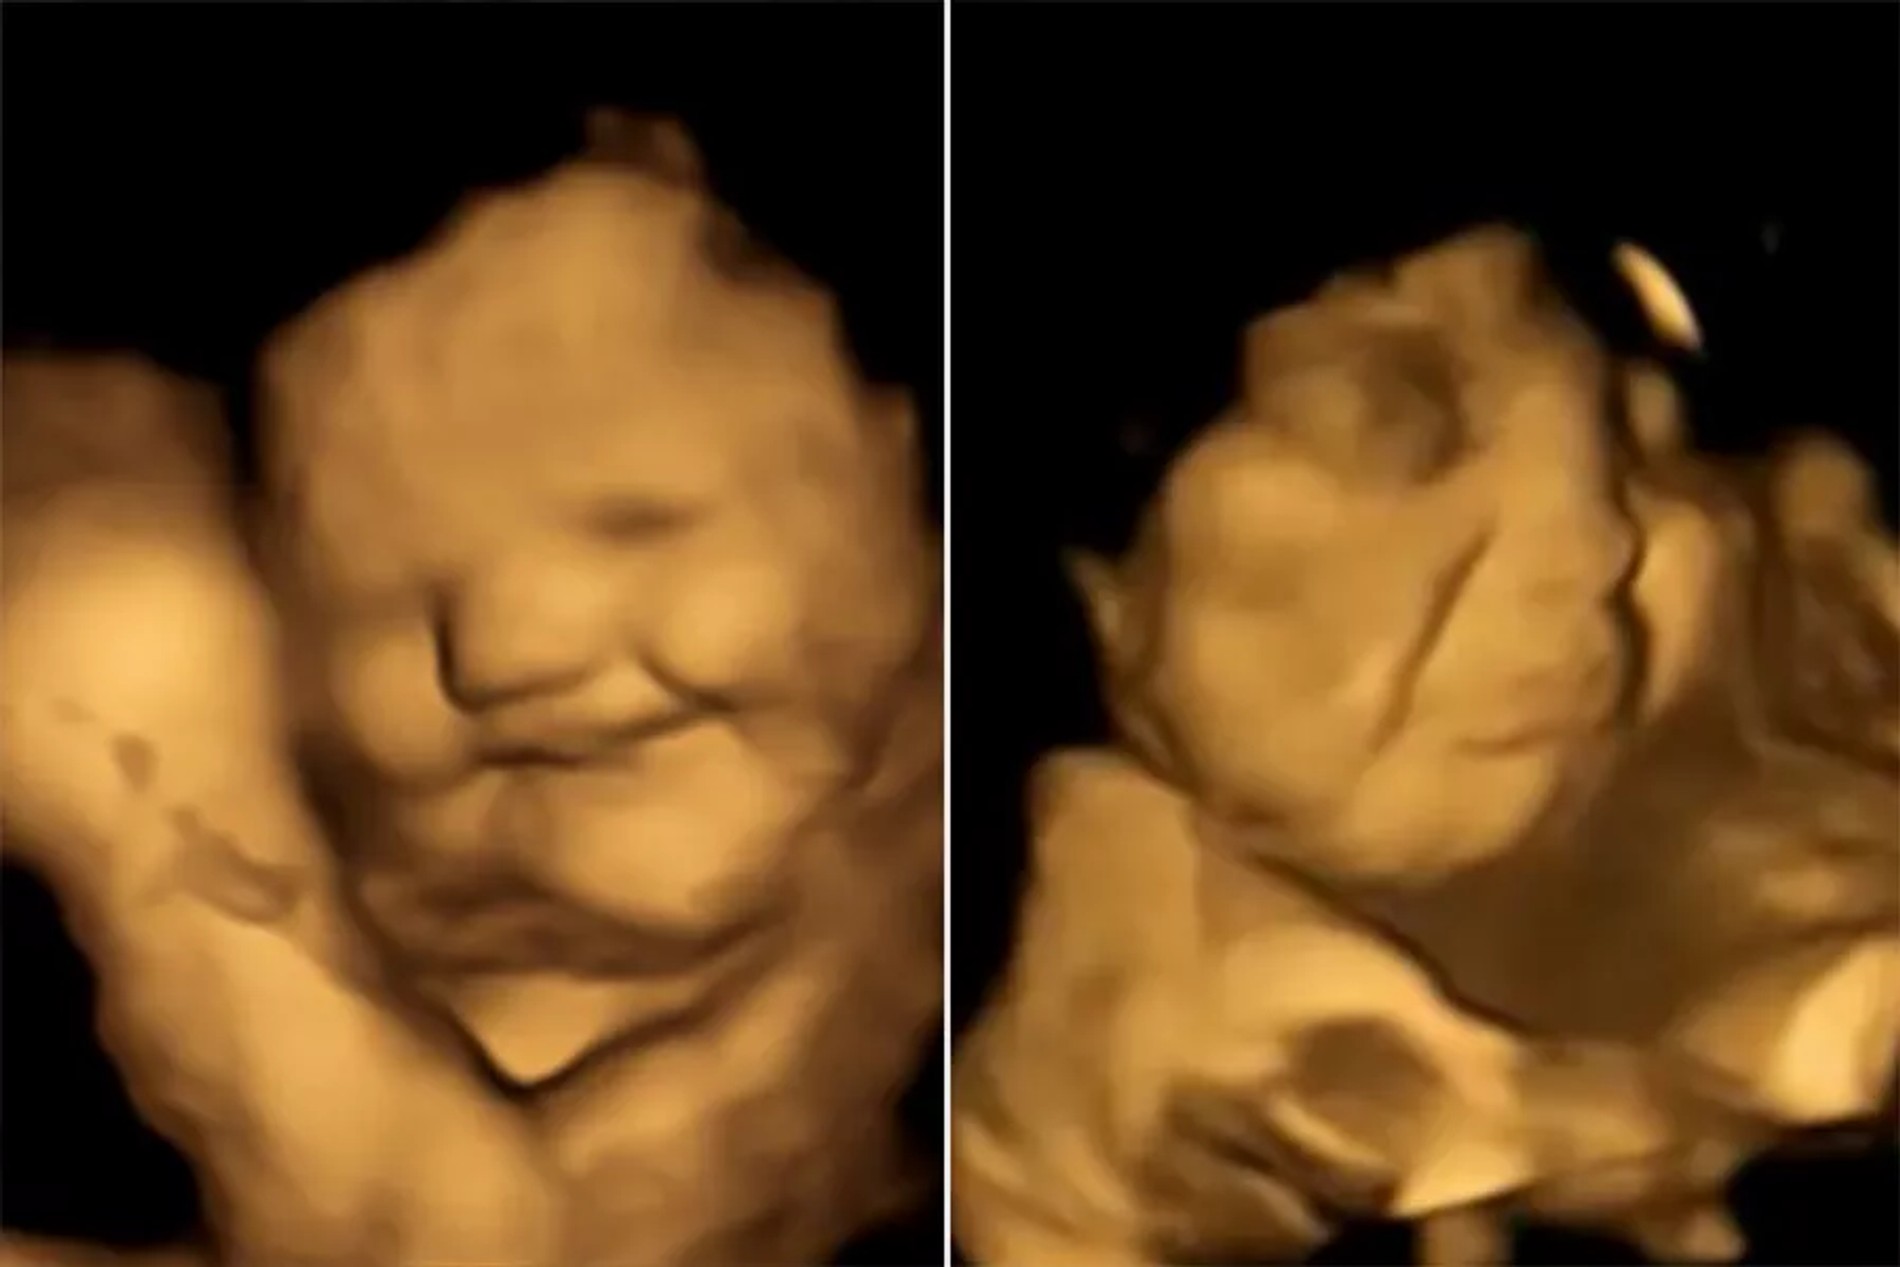

Британские ученые (да-да, именно они!) провели интересное и, можно даже сказать, милое исследование. Они решили выяснить, какие продукты нравятся младенцам в утробе матери, а какие нет. Для этого с помощью аппаратов УЗИ следили за реакцией малышей в то время, когда их мамы пробовали разные продукты.

К примеру, от моркови на лицах детей появлялась улыбка. Когда же женщины ели капусту, их малыши начинали гримасничать. Все испытуемые находились на 32-36 неделях. На более серьезных сроках, по словам ученых, разглядеть эмоции ребенка на еду уже гораздо сложнее. Да и это исследование — первое такое в истории.